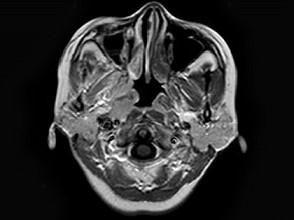

问题 女,34岁。右侧听力下降,耳鸣2个月。MRI平扫及增强扫描如图示,最可能的诊断是 ( )

选项 A、动脉瘤 B、未见异常 C、脑膜瘤 D、神经源性肿瘤 E、鼻咽癌

答案 E